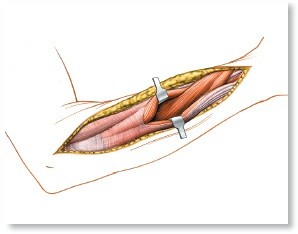

* Approach: The radius is typically approached via a volar (Henry) approach to allow for optimal plate placement on the flat tension surface, while the ulna is approached directly over its subcutaneous border.